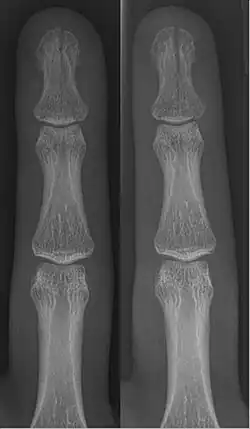

- Broken finger – a fracture of the carpal phalanges

Occasionally, smaller bones, such as phalanges of the toes and fingers, may be treated without the cast, by buddy wrapping them, which serves a similar function to making a cast. A device called a Suzuki frame may be used in cases of deep, complex intra-articular digit fractures.[40] By allowing only limited movement, immobilization helps preserve anatomical alignment while enabling callus formation, toward the target of achieving union.

In children, whose bones are still developing, there are risks of either a growth plate injury or a greenstick fracture.

- A greenstick fracture occurs due to mechanical failure on the tension side. That is, since the bone is not so brittle as it would be in an adult, it does not completely fracture, but rather exhibits bowing without complete disruption of the bone's cortex in the surface opposite the applied force.